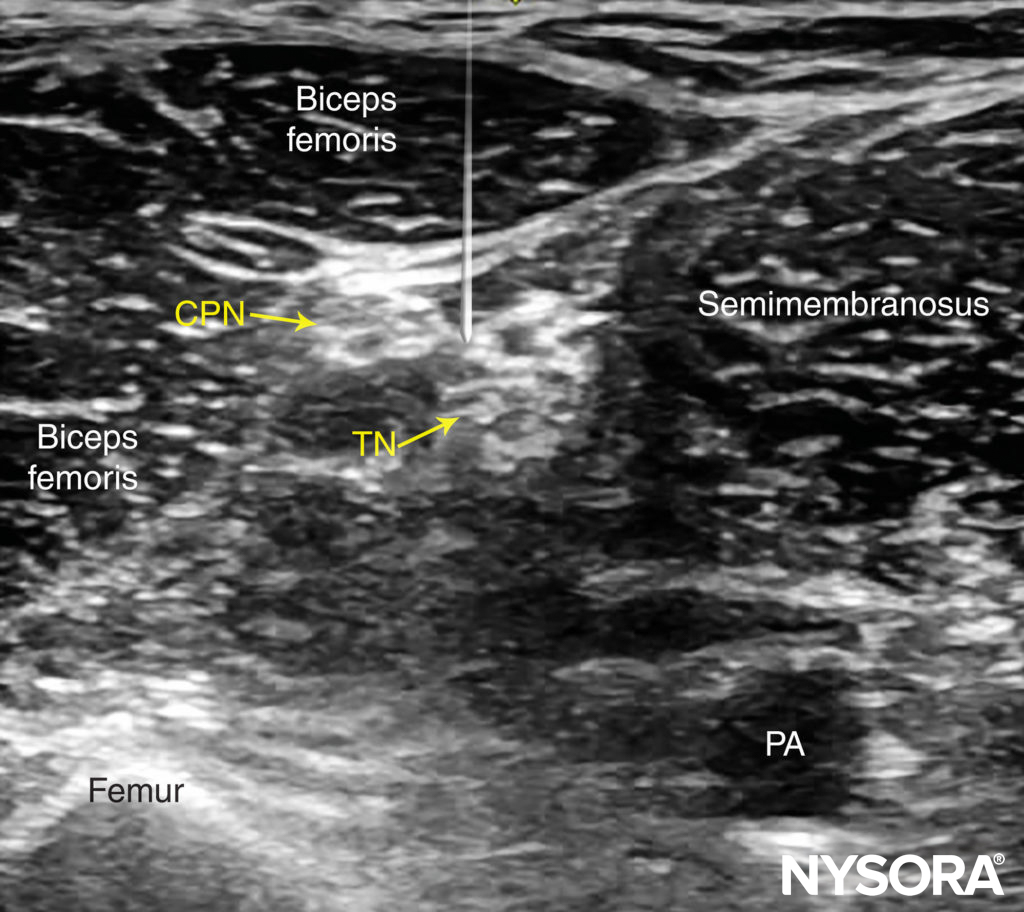

Beginning with the transducer in the transverse position at the popliteal crease, the popliteal artery is identified, aided with color Doppler US when necessary, at a depth of approximately 3–4 cm. The popliteal vein accompanies the artery at it is positioned just superficial (posterior) to it. On either side of the artery are the biceps femoris muscles (laterally) and the semimembranosus and semitendinosus muscles (medially). The tibial nerve is positioned superficial and lateral to the vein and is seen as a hyperechoic, oval or round structure with a honeycomb pattern (Figure 3). Asking the patient to dorsiflex and plantar flex the ankle makes the two sciatic nerve branches twist or move in relation to each other. Usually, tilting the transducer caudally is necessary to bring out the nerve from the neighboring adipose tissue.

FIGURE 3. Sonoanatomy of the sciatic nerve at the popliteal fossa. The two main divisions of the sciatic nerve, the tibial nerve (TN) and the common peroneal nerve (CPN), are seen immediately lateral and superficial to the popliteal vein (PV) and artery (PA). This image was taken at 5 cm above the popliteal fossa crease, where the TN and CPN have just started diverging.